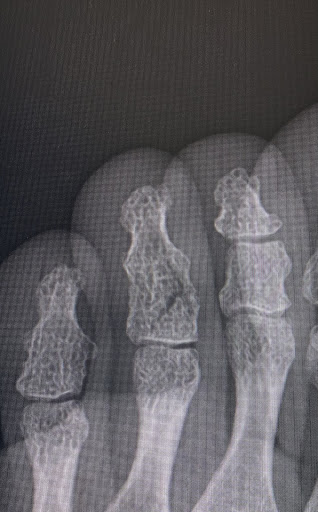

足の中指を骨折し、1日でも早く走れるようになりたくて来院しました。

こちらでは骨の癒着を早める治療器があり、しかも保険適用になるので可能な限り毎日通いつめて約2週間後のレントゲンが2枚目になります。

治療経過はかなり良好だと思います。

また、初診時に歩き方のコツやテーピングのコツなど、病院ではあまりしっかり教えてもらえなかったところまで詳しく話してくださったおかげで“うっかりやってしまわない方がいい動き”も最小限にできていると思います。

このまま1日も早い完治を目指して、しっかり通おうと思います。